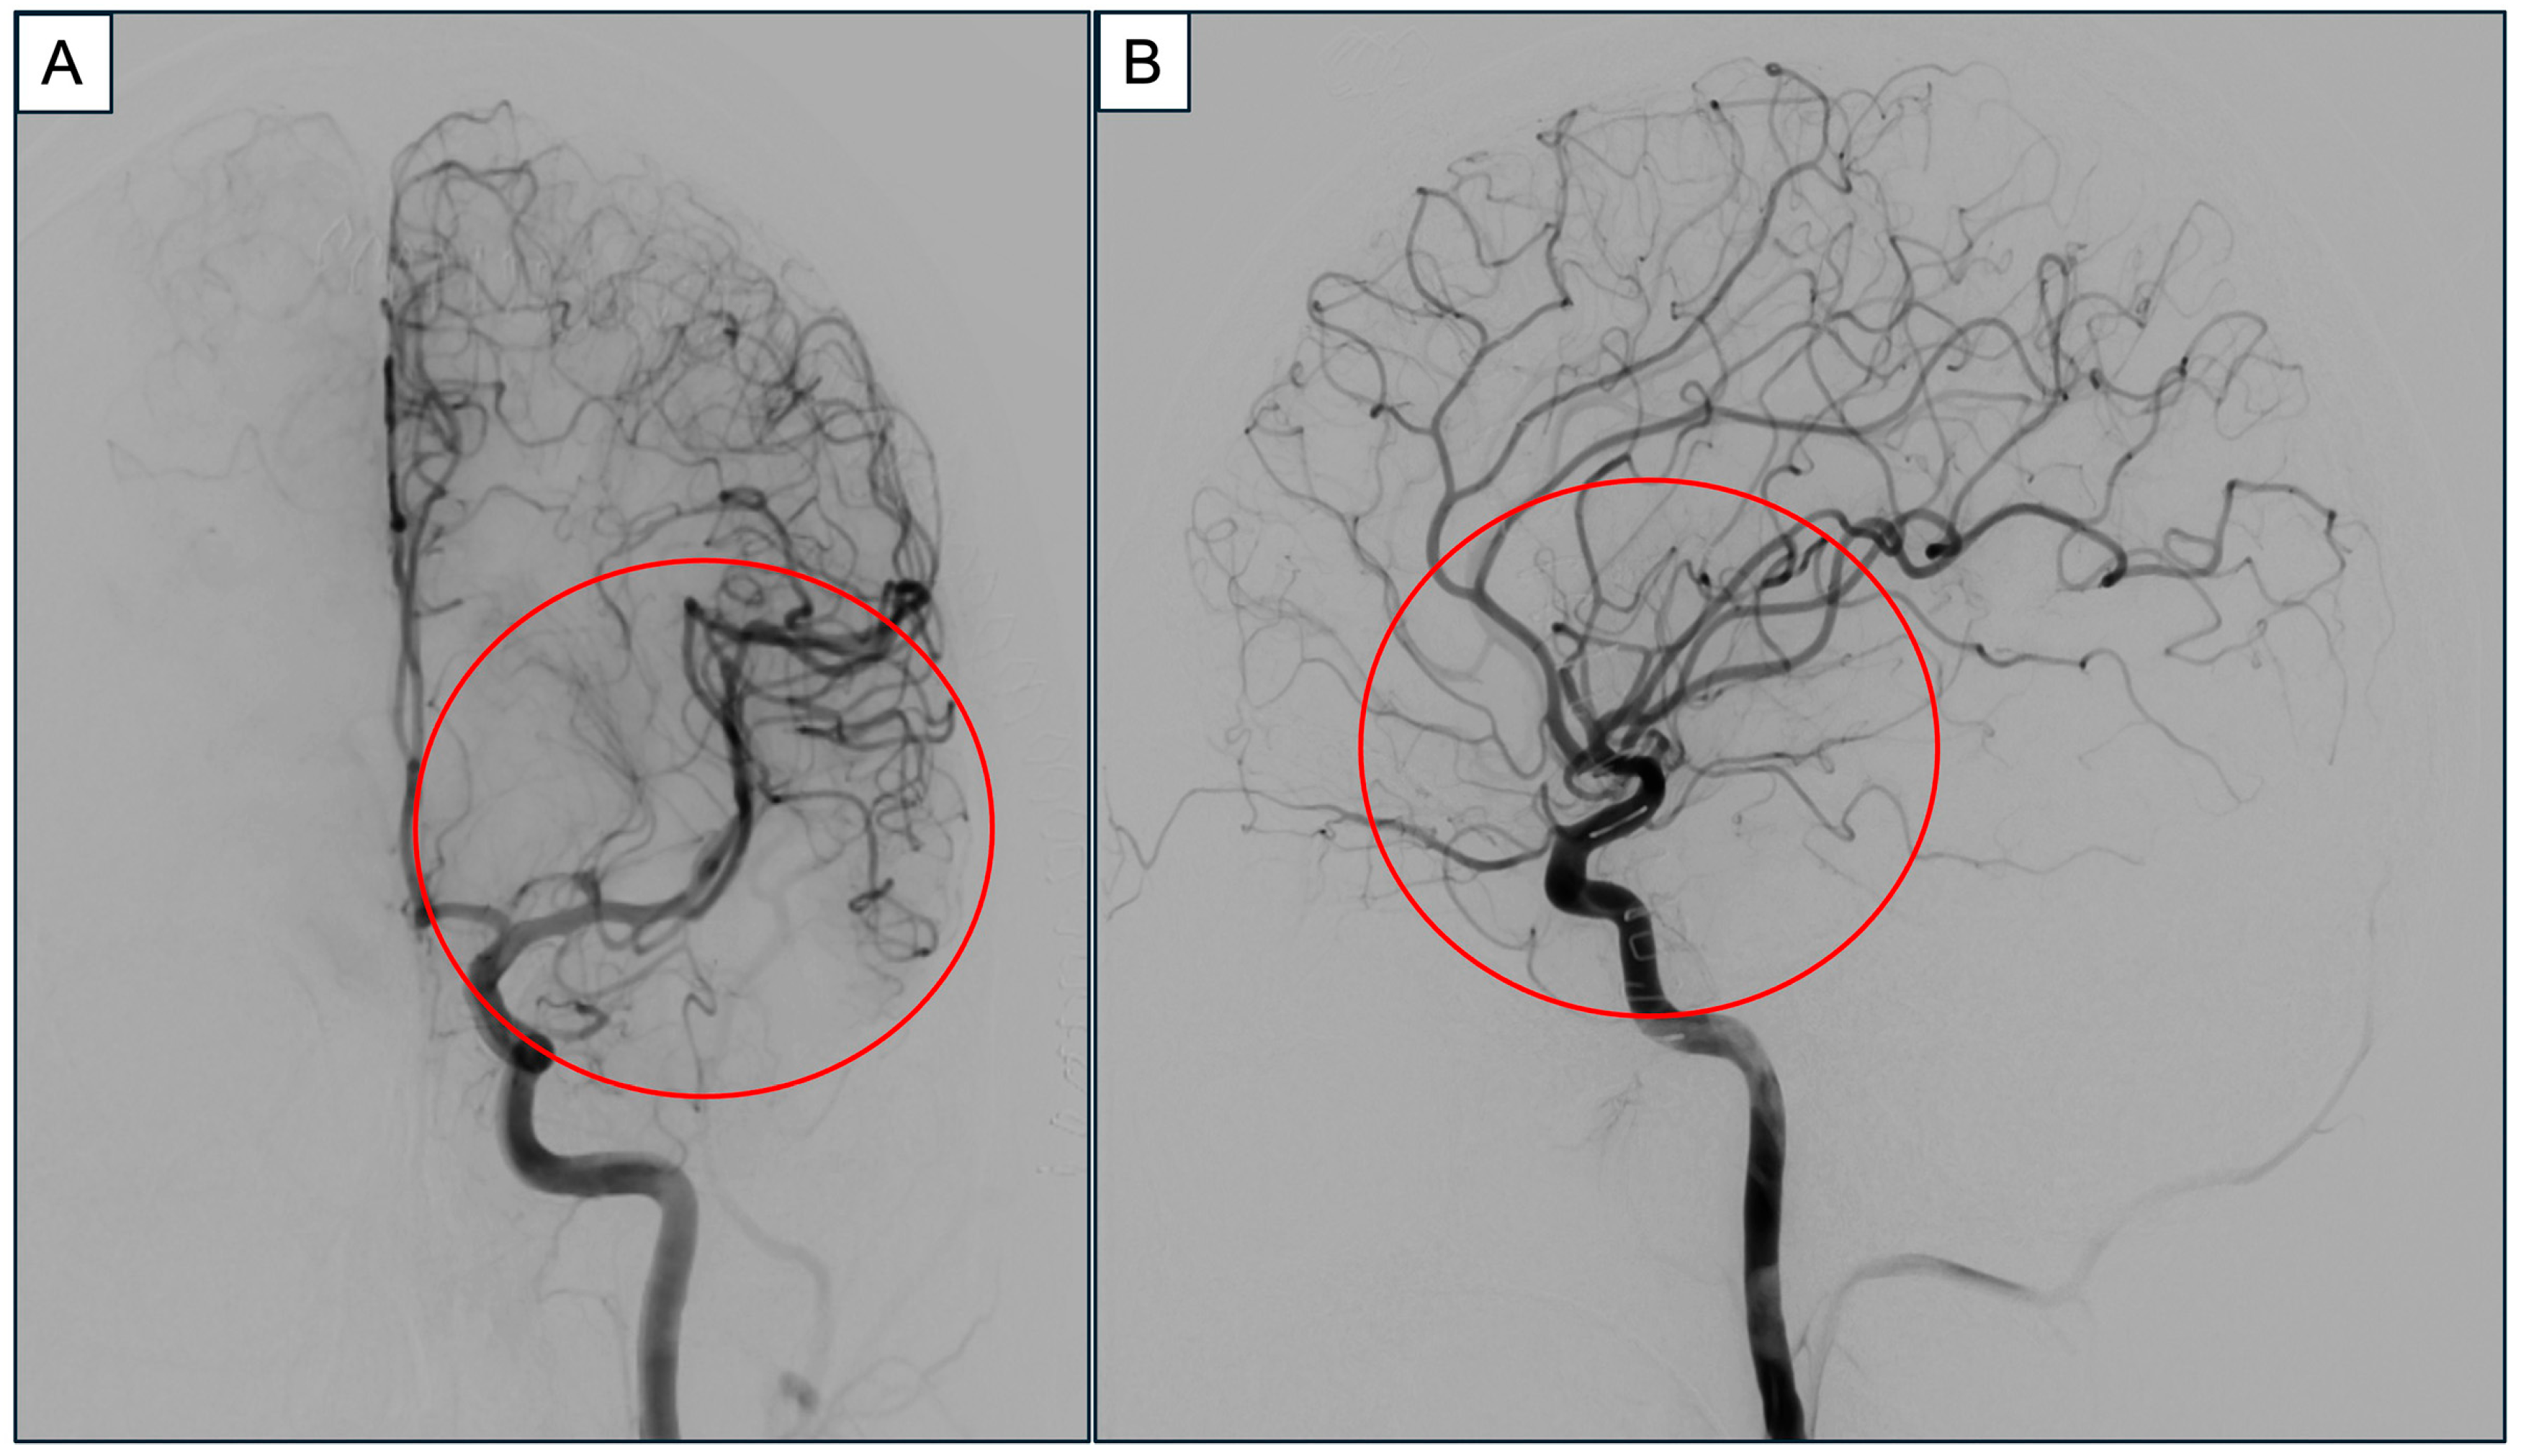

2. Case Report